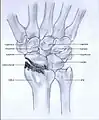

Post-traumatic osteoarthritis can be classified into four stages.[1][6] These stages are similar between SLAC and SNAC wrists. Each stage has a different treatment.

- Stage I: the osteoarthritis is only localized in the distal scaphoid and radial styloid.

- Stage II: the osteoarthritis is localized in the entire radioscaphoid joint.

- Stage III: the osteoarthritis is localized in the entire radioscaphoid joint with involvement of the capitolunate joint.

- Stage IV: the osteoarthritis is located in the entire radiocarpal joint and in the intercarpal joints. It also may involve the distal radio-ulnar joint (DRUJ).

Stage II